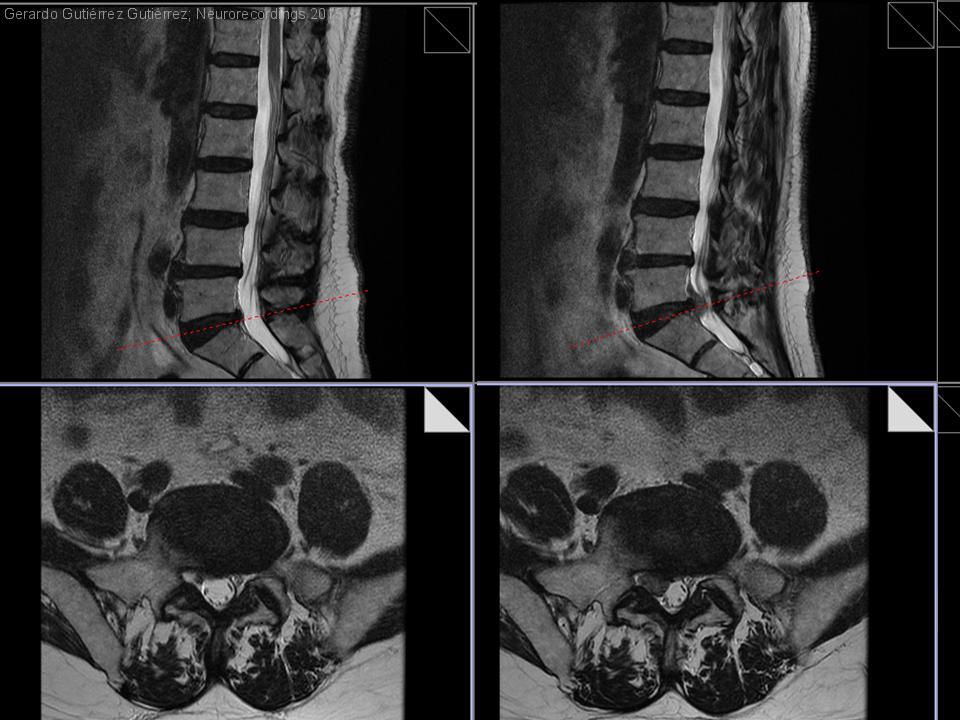

Hernia posterolateral L5-S1 con radiculopatía L5, evolución en RMN y hallazgos neurofisiológicos

Diagnóstico final: Hernia L5-S1 radiculopatía L5